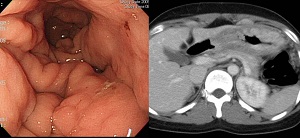

º¸¸¸ 4Çü ÁøÇ༺ À§¾Ï¿¡¼­ ¾Ï¼¼Æ÷´Â À§Á¡¸· ¾Æ·¡¿¡¼­ ³Ð°Ô ħÀ±Çϱ⠶§¹®¿¡ Á¡¸·ÁÖ¸§ÀÌ µÎ²¨¿öÁö¸é¼­ ÁÖ¸§ »çÀÌÀÇ °ñÂ¥±â ¹Ù´Úµµ ¿Ã¶ó¿À°Ô µË´Ï´Ù. ±× °á°ú Á¤»ó ÁÖ¸§ »çÀÌ»çÀÌ °ñÂ¥±âÀÇ ±íÀ̰¡ ¾è¾ÆÁý´Ï´Ù. °ñÂ¥±âÀÇ Æøµµ Á¼¾ÆÁý´Ï´Ù.

Stomach, total gastrectomy

Advanced gastric carcinoma

1. Location : [1] upper third, [2] middle third, Center at high body, anterior wall

2. Gross type : Borrmann type 4

3. Histologic type : undifferentiated carcinoma

4. Histologic type by Lauren : diffuse

5. Size : 13.5cm x encircled

6. Depth of invasion : invades serosa (pT4a)

7. Resection margin: free from carcinoma, safety margin: proximal 2 cm, distal 8 cm

8. Lymph node metastasis : metastasis to 2 out of 40 regional lymph nodes (pN1)

9. Lymphatic invasion : present

10. Venous invasion : not identified

11. Perineural invasion : present

12. Peritoneal cytology : negative

13. AJCC stage by 7th edition: T4a N1